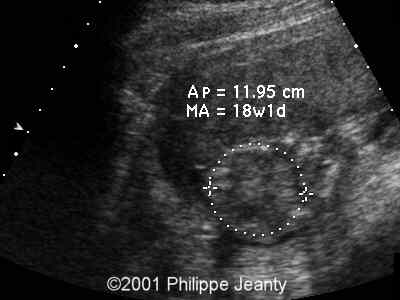

Durante la gravidanza, le donne possono essere sottoposte a screening mediante prelievo di villi coriali (villocentesi) e amniocentesi per rilevare la trisomia 16. Con l'avvento delle tecniche non invasive per la rilevazione dell'aneuploidia, lo screening prenatale con test che utilizzano il sequenziamento di nuova generazione può essere utilizzato prima delle tecniche invasive. Ciò può causare un ritardo della crescita fetale.